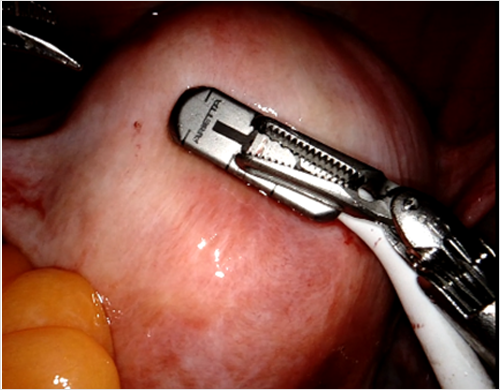

학회가 전하는 초음파 소식 Ultrasound in the Assessment of Obstetric hemorrhage and Postpartum Uterine Abnormalities 2026-02-02 부인과 수술에서 수술 중 초음파(IOUS)의 역할과 최신 임상 응용 2026-01-06 New insights into functional imaging of the placenta 2025-12-01 더보기